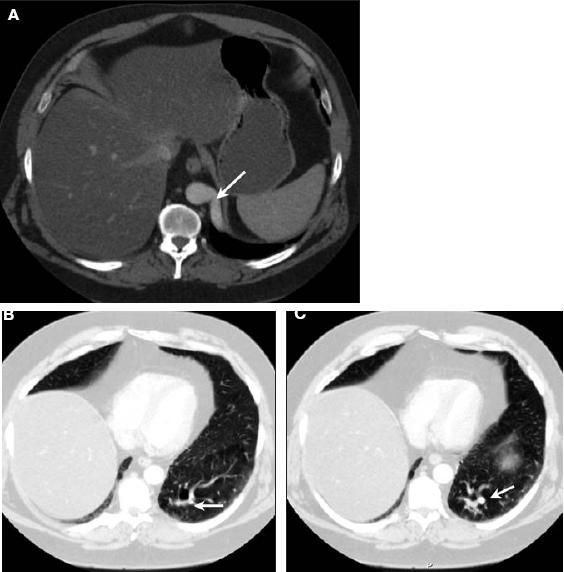

Findings on a CT angiogram of the chest confirmed the vascular nature of the abnormality that was seen on the abdominal CT scan, with minimal bronchoparenchymal abnormalities (Figure 1). Pulmonary and aortic angiography was performed (Figure 2). The results were as follows:

Figure 1 – CT angiogram of the chest showed an arterial feeding vessel (arrow) arising from the descending aorta within the posterior basal segment of the left lower lobe (A, B, and C). There are multiple prominent vessels, and both ground-glass and cystic changes are seen in the surrounding lung parenchyma (lung window settings, B and C).